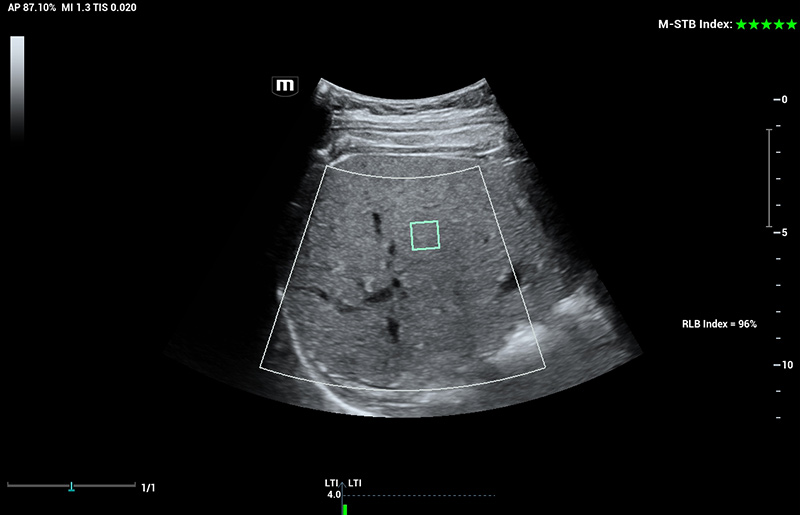

Com tecnologia ZST+

A plataformaZST+ representa um salto extraordinĂĄrio na tecnologia de ultrassom, passando da tradicional forma??o de feixe para o processamento de dados de canal. Essa inova??o revolucionĂĄria supera as compensa??es tradicionais entre resolu??o espacial, resolu??o temporal e uniformidade do tecido, resultando em uma qualidade de imagem inigualĂĄvel com infinitas solu??es de gera??o de imagens.

O Resona I9 fornece solu??es clĂnicas abrangentes para aplica??es dedicadas. Com base em percep??es aprofundadas em diferentes cenĂĄrios clĂnicos, ele oferece inova??es que fornecem aos usuĂĄrios extrema clareza, inteligĂȘncia excepcional e confian?a excepcional no diagnĂłstico.